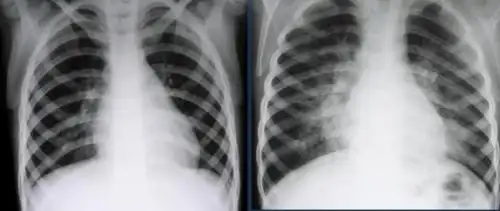

小孩四岁发烧不退诊断为肺炎,帮忙看下两次片子是否好了

请教:6岁,胸片上肺炎,站立位和躺着拍的范围为什么不一样呢